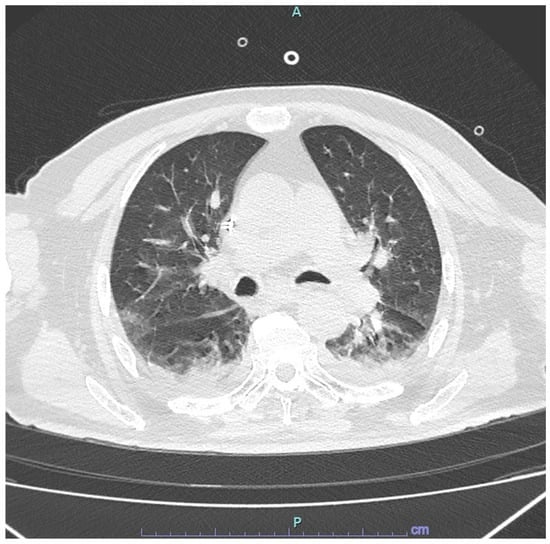

A Case of Severe Respiratory Failure Caused by Metapneumovirus and Influenza Virus in a Patient with HIV Infection

2. Case Presentation